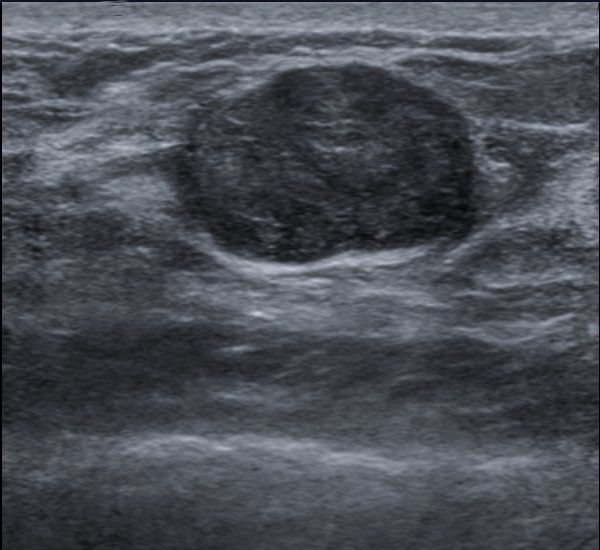

Fibroadenoma is a benign tumor of the breast. It consists of epithelium and stroma. It usually occurs between the age of 15 to 35 years. It is more common in females than in males. Males on anti-androgen therapy may develop fibroadenoma. Fibroadenoma is a hormone-dependent tumor. Hence, it increases in size during pregnancy and decreases in size after menopause. Treatment mainly involves observation. Breast examination and investigations are repeated every 3 to 6 months. In enlarging tumors, surgical excision is indicated. Cryoablation is an alternative to surgery. Reference: https://step2.medbullets.com/gynecology/120421/fibroadenoma Image via: https://step2.medbullets.com/gynecology/120421/fibroadenoma